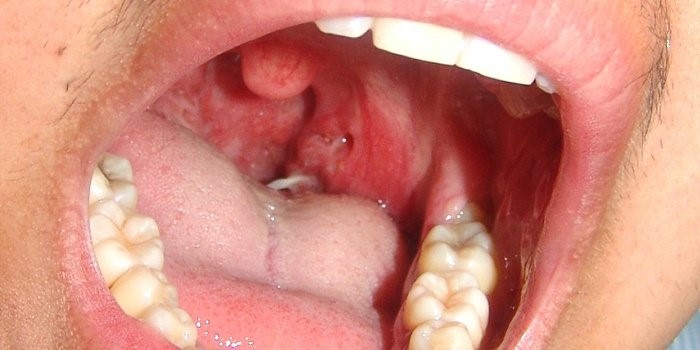

Перечисленные симптомы могут проявиться в незначительных количествах у женщин, а также у мужчин, однако они в значительной мере понижают качество повседневной жизни. Обратив на них внимание, есть больший шанс приостановить текущий патологический процесс и замедлить наступление следующего этапа развития болезни. Для представления о том, какие изменения происходят в организме, в частности, в тканях горла, когда выявляется рак горла первые симптомы фото помогут наглядно увидеть наглядно текущие ухудшения. Зная, как проявляется рак горла симптомы которого будут перечислены ниже, можно вовремя обнаружить возникновение патологического процесса.

У мужчин проявляется рак горла также при длительном кашле, если отсутствует вредная привычка курение. Именно в этом случае на кашель сразу же обращается внимание и проводится диагностика общего состояния больного. И хотя у женщин данная вредная привычка встречается не так часто, однако именно курение часто не дает вовремя обнаружить текущее заболевание: именно ему приписываются такие проявления, как кашель, ухудшение общего внешнего вида, потеря аппетита и снижение веса. Симптомы рака горла на фото помогут более наглядно увидеть и оценить степень поражения даже при начальных стадиях онкологического процесса текущего в области горла и шеи. Также, отвечая на вопрос, как проявляется рак горла, следует учитывать, что проявления текущего процесса напрямую зависят от типа рака горла и гортани: имеется определенная классификация, позволяющая отнести данное заболевание к определенному типу с сопровождающими его симптомами. Это влияет на выбор систему лечебного воздействия.

Как выглядит начальная стадия рака в горле?

На начальных стадиях раковые новообразования могут выглядеть как небольшие бугорки, расположенные на слизистой оболочке горла. В дальнейшем, по мере распада патологически измененной ткани, на их месте образовываются язвы.